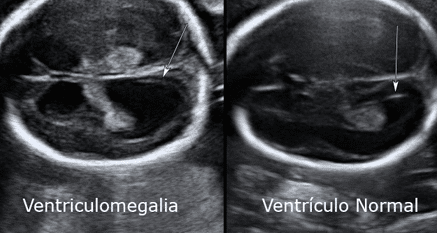

Ventriculomegalia fetal leve: diagnóstico, avaliação e conduta

A ventriculomegalia é definida como a dilatação dos ventrículos cerebrais fetais e é um achado relativamente comum na ultrassonografia pré-natal.…